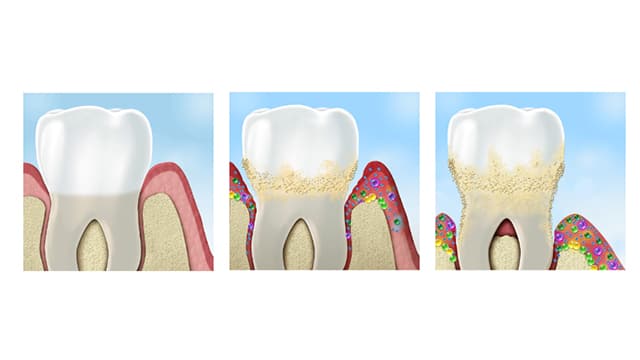

Plaque & Tartar

Plaque: What Is It and How do I Get Rid of It?

By following easy steps for keeping your teeth and gums healthy – plus seeing your dentist regularly — you can have your teeth for a lifetime!

Plaque & Tartar

What Causes Plaque On Teeth?

When left alone, plaque on teeth turns to tartar and can increase your risk for cavities or gum disease. And as scary as it sounds, it happens to everyone.

Read More